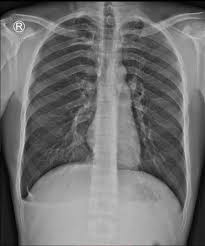

Pneumothorax / Case Report Covid 19 Associated Bilateral Spontaneous Pneumothorax A Literature Review In The American Journal Of Tropical Medicine And Hygiene Volume 103 Issue 3 2020 / Tension pneumothorax most commonly occurs in people with penetrating chest injuries.. This may be caused by physical trauma to the lung, such as a wound. Pneumothorax nursing interventions, treatment, pathophysiology nclex review for the different types of pneumothorax: There are several variations of pneumothorax. Pneumothorax is the medical term for a collapsed lung, a condition in which air or gas is trapped in the space surrounding the lungs causing the lungs to collapse. Also known as pneumothorax, collapsed lung is a rare condition that may cause chest pain and make it hard to breathe.

This is termed spontaneous pneumothorax. Pneumothoraces can be even further classified as simple, tension, or open. Pneumothorax nursing interventions, treatment, pathophysiology nclex review for the different types of pneumothorax: Pneumothorax, also called a collapsed lung, is when air gets between one of your lungs and the wall of your chest. It is reasonably common and has many different causes.

Scielo Brasil Pneumothorax As A Late Complication Of Covid 19 Pneumothorax As A Late Complication Of Covid 19 from minio.scielo.br In tension pneumothorax, patients are distressed with rapid laboured respirations, cyanosis, profuse diaphoresis, and tachycardia. The definition of a pneumothorax is an accumulation of air outside the lungs, but inside the chest wall. Tension pneumothorax most commonly occurs in people with penetrating chest injuries. In a healthy body, the lungs are touching the walls of the chest. Patients with a pneumothorax typically report dyspnoea and chest pain. A pneumothorax occurs when air leaks into the space between the lung and chest wall (called the pleural space). A small pneumothorax may cause few or no symptoms. Pneumothorax occurs when air enters the space around your lungs (the pleural space).

Other signals that the problem may be a collapsed lung are: Normally, the outer surface of the lung sits next to the inner surface of the chest wall. The lung and the chest wall are covered by thin membranes called pleura. It occurs when air accumulates between the parietal and visceral pleura inside the chest. Pneumothoraces can be even further classified as simple, tension, or open. A pneumothorax is an abnormal collection of air in the pleural space between the lung and the chest wall. Pneumothorax is defined as the presence of air or gas in the pleural cavity (ie, the potential space between the visceral and parietal pleura of the lung), which can impair oxygenation and/or. A pneumothorax occurs when air leaks into the space between your lung and chest wall. The pressure causes the lung to give way, at least partly. Pneumothorax is classified as spontaneous or traumatic. Hemothorax occurs when there is blood in that. This air pushes on the lung, which makes it collapse. The air accumulation can apply pressure on the lung and make it collapse.

In a healthy body, the lungs are touching the walls of the chest. A pneumothorax is a collection of air outside the lung but within the pleural cavity. It is reasonably common and has many different causes. Open pneumothorax vs closed pneumothorax. Pneumothorax, also called a collapsed lung, is when air gets between one of your lungs and the wall of your chest.

Patients with a pneumothorax typically report dyspnoea and chest pain. Pneumothoraces can be even further classified as simple, tension, or open. Pneumothorax is defined as the presence of air or gas in the pleural cavity (ie, the potential space between the visceral and parietal pleura of the lung), which can impair oxygenation and/or. In a healthy body, the lungs are touching the walls of the chest. The definition of a pneumothorax is an accumulation of air outside the lungs, but inside the chest wall. It is reasonably common and has many different causes. A pneumothorax is a collection of air outside the lung but within the pleural cavity. A pneumothorax can be a complete lung collapse or a collapse of only a portion of the lung. A pneumothorax occurs when air leaks into the space between the lung and chest wall (called the pleural space). This air pushes on the lung, which makes it collapse. Also known as pneumothorax, collapsed lung is a rare condition that may cause chest pain and make it hard to breathe. A large pneumothorax can squash the lung and cause it to collapse. This is termed spontaneous pneumothorax.